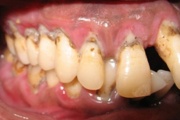

GAgP 25 aastasel suitsetaval puuduliku suuhügieeniga patsiendil